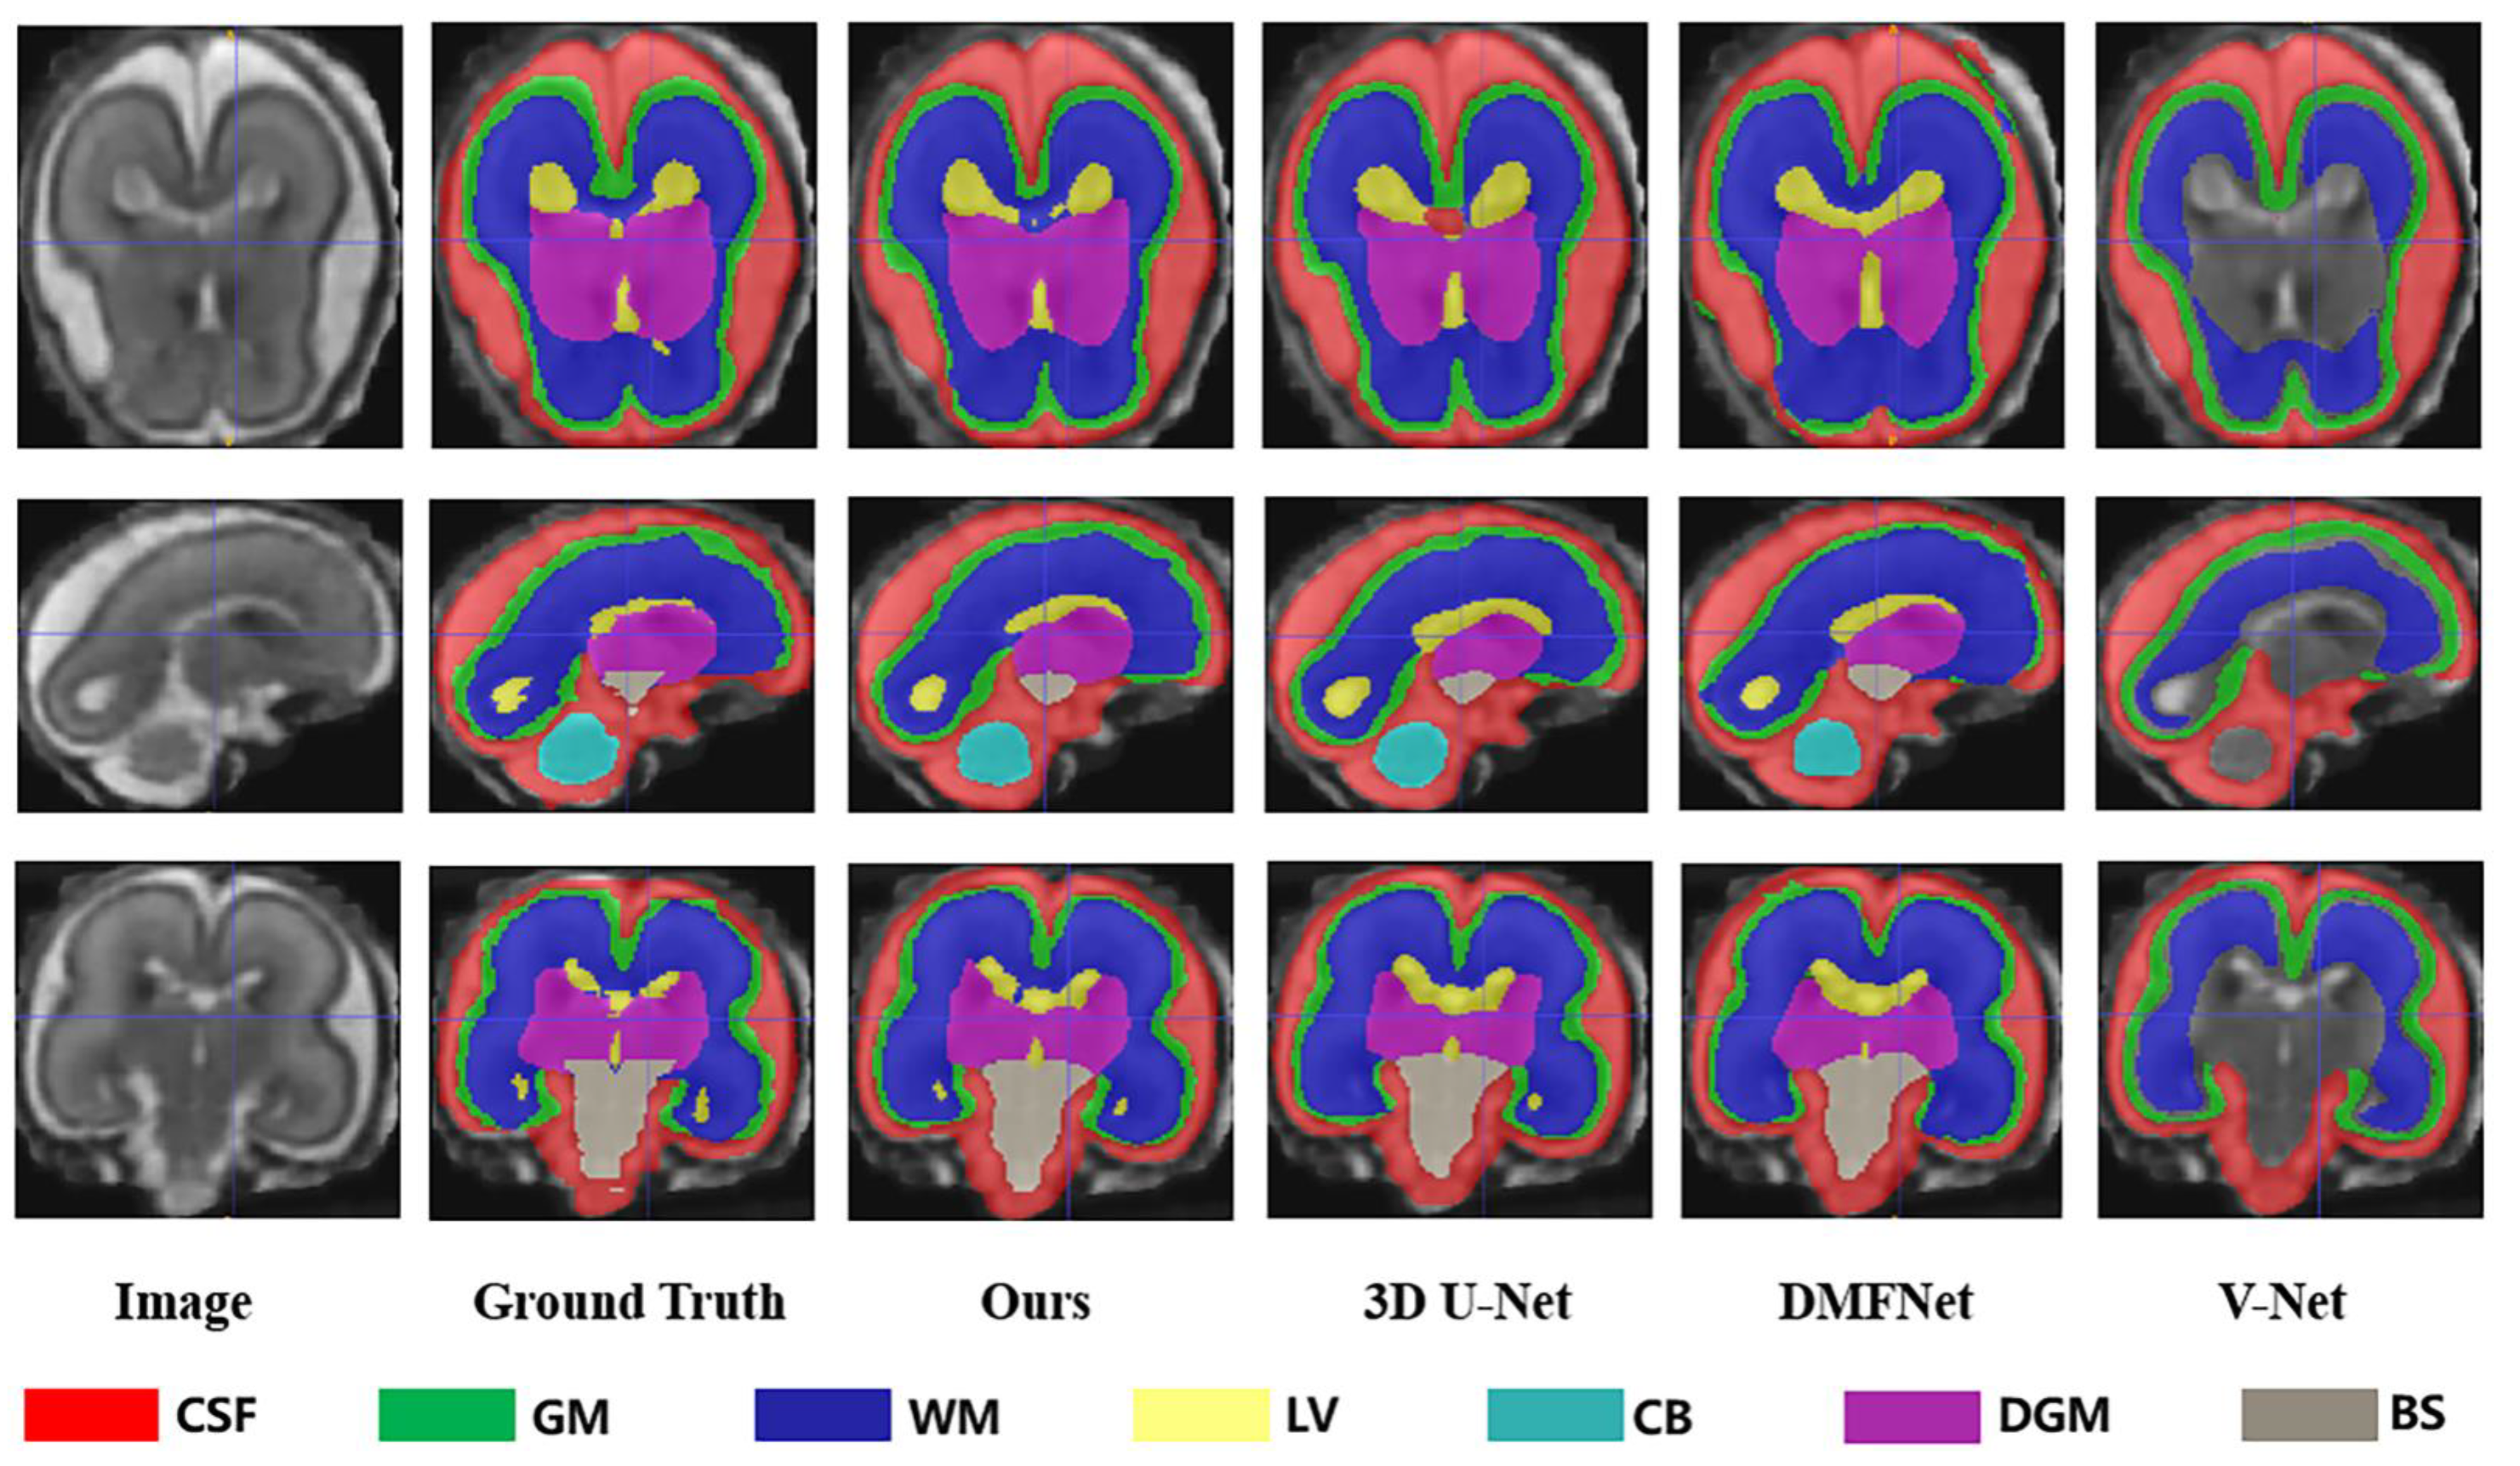

As demonstrated in Table 1, based on all evaluation metrics, overall, our method outperformed the other methods with the best average segmentation on 7 tissues. DSC, VS, PRE, SEN, and SPC all achieved the highest values with (83.79 ± 3.36)%, (84.84 ± 3.23)%, (85.73 ± 3.75)%, (84.32 ± 5.22)%, and (99.33 ± 0.15)%, and HD95 achieved the smallest with (35.66 ± 2.07) mm. In terms of different tissues, our method got better evaluation metrics in cerebrospinal fluid, gray matter, ventricle, cerebellum, and brainstem, whereas the best segmentation on white matter and dark gray matter were obtained with 3D U-Net. Unexpectedly, the ventricles, cerebellum, deep gray matter, and brainstem were not fully segmented in V-Net. We showed examples for visual comparison in Figure 4. Taking the ventricle as an example, it can be seen that only our method better identified the boundary between it and other tissues, such as white matter and deep gray matter, which was the result closest to the ground truth, whereas other methods either blurred the boundary or failed to find the ventricle part. Figure 5 depicted box plots to further visualize the differences in the Dice results. We have seen that the segmentation effect of the four models on CSF was relatively good, and Dice values were concentrated in a high range (0.8–0.9). For gray matter and white matter segmentation, the interquartile range (IQR) of DMFNet and V-Net was large, indicating a more dispersed distribution of Dice values. Table 2 showed the number of parameters and FLOPs for the four models. Our parameters were 24.21 M smaller than 3D U-Net, and FLOPs were reduced by 85.94%. DMFNET had the lowest number of parameters and FLOPs, but its segmentation performance was much lower than our method and 3D U-Net. Therefore, combining the results in Table 1 and Table 2 demonstrated that our network was a better model in the comprehensive evaluation of segmentation performance and computing resource utilization.

Figure 4.

Segmentation results of different methods (Ours, 3DU-Net, DMFNet and V-Net) in axial, sagittal and coronal planes respectively.